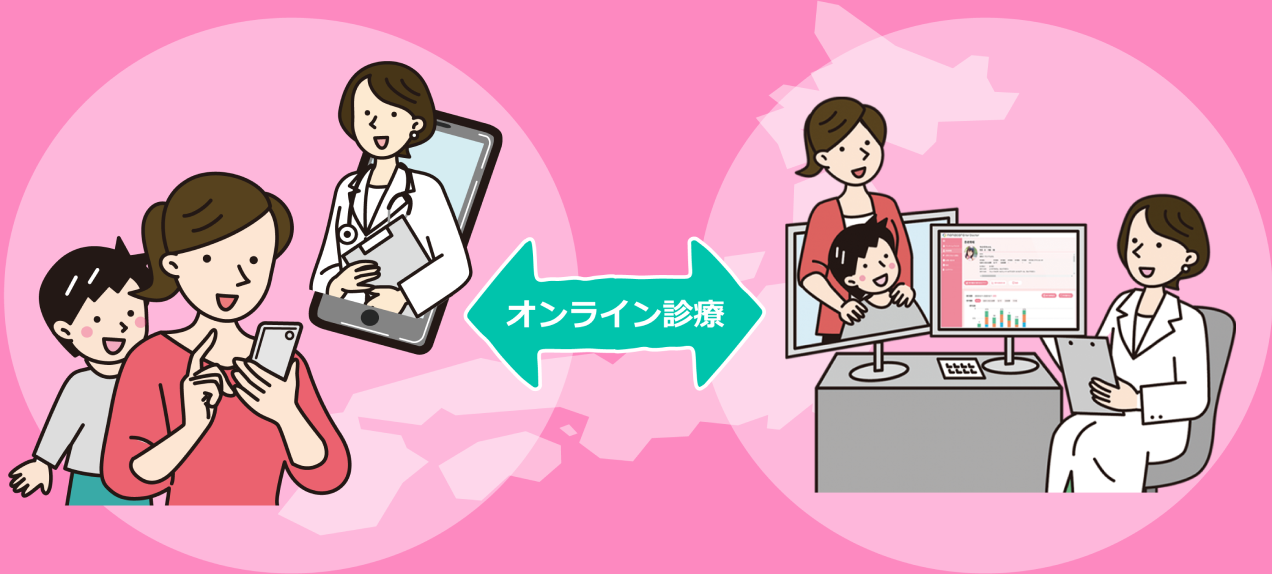

通院が難しいあの患者さんへできること。

そろそろ、オンライン診療、はじめませんか?

てんかん診療に特化したオンライン診療サービス

ナナメディ

オンライン診療は、これまで様々な理由でアクセスできなかったてんかん患者・ご家族に対して適切な医療を提供できる可能性があります。